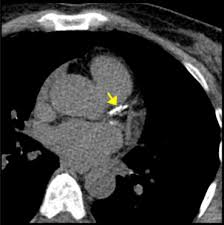

Heavily calcified stenosis of the mid-right coronary artery at baseline A and after percutaneous coronary intervention with RA 125 and 15mm burrs and drug-eluting stent implantation B. The presence of calcium in coronary arteries is almost always indicative of atherosclerotic plaque but bears no relationship to plaque stability or instability. Atheroma calcification is a common feature of advanced atherosclerosis however with the advent of CT scanning it has become possible to detect extensive coronary calcification in the absence of flow-limiting lesions.

People with coronary artery disease will have calcification of the blood vessels. Other components of the novel. Atheroma calcification is a common feature of advanced atherosclerosis however with the advent of CT scanning it has become possible to detect extensive coronary calcification in the absence of flow-limiting lesions. Researchers suggest that 90 of. Heavily calcified stenosis of the mid-right coronary artery at baseline A and after percutaneous coronary intervention with RA 125 and 15mm burrs and drug-eluting stent implantation B. The coronary artery calcium score is considered the most useful marker for predicting coronary events. There was no ECG gating. Coronary artery calcification pathologically begins as microcalcifications 05 to 150 μm and grows into larger calcium fragments which eventually result in sheet-like deposits 3 mm. Cardiac risk factors and insulin resistance lead to progression of coronary artery calcification.